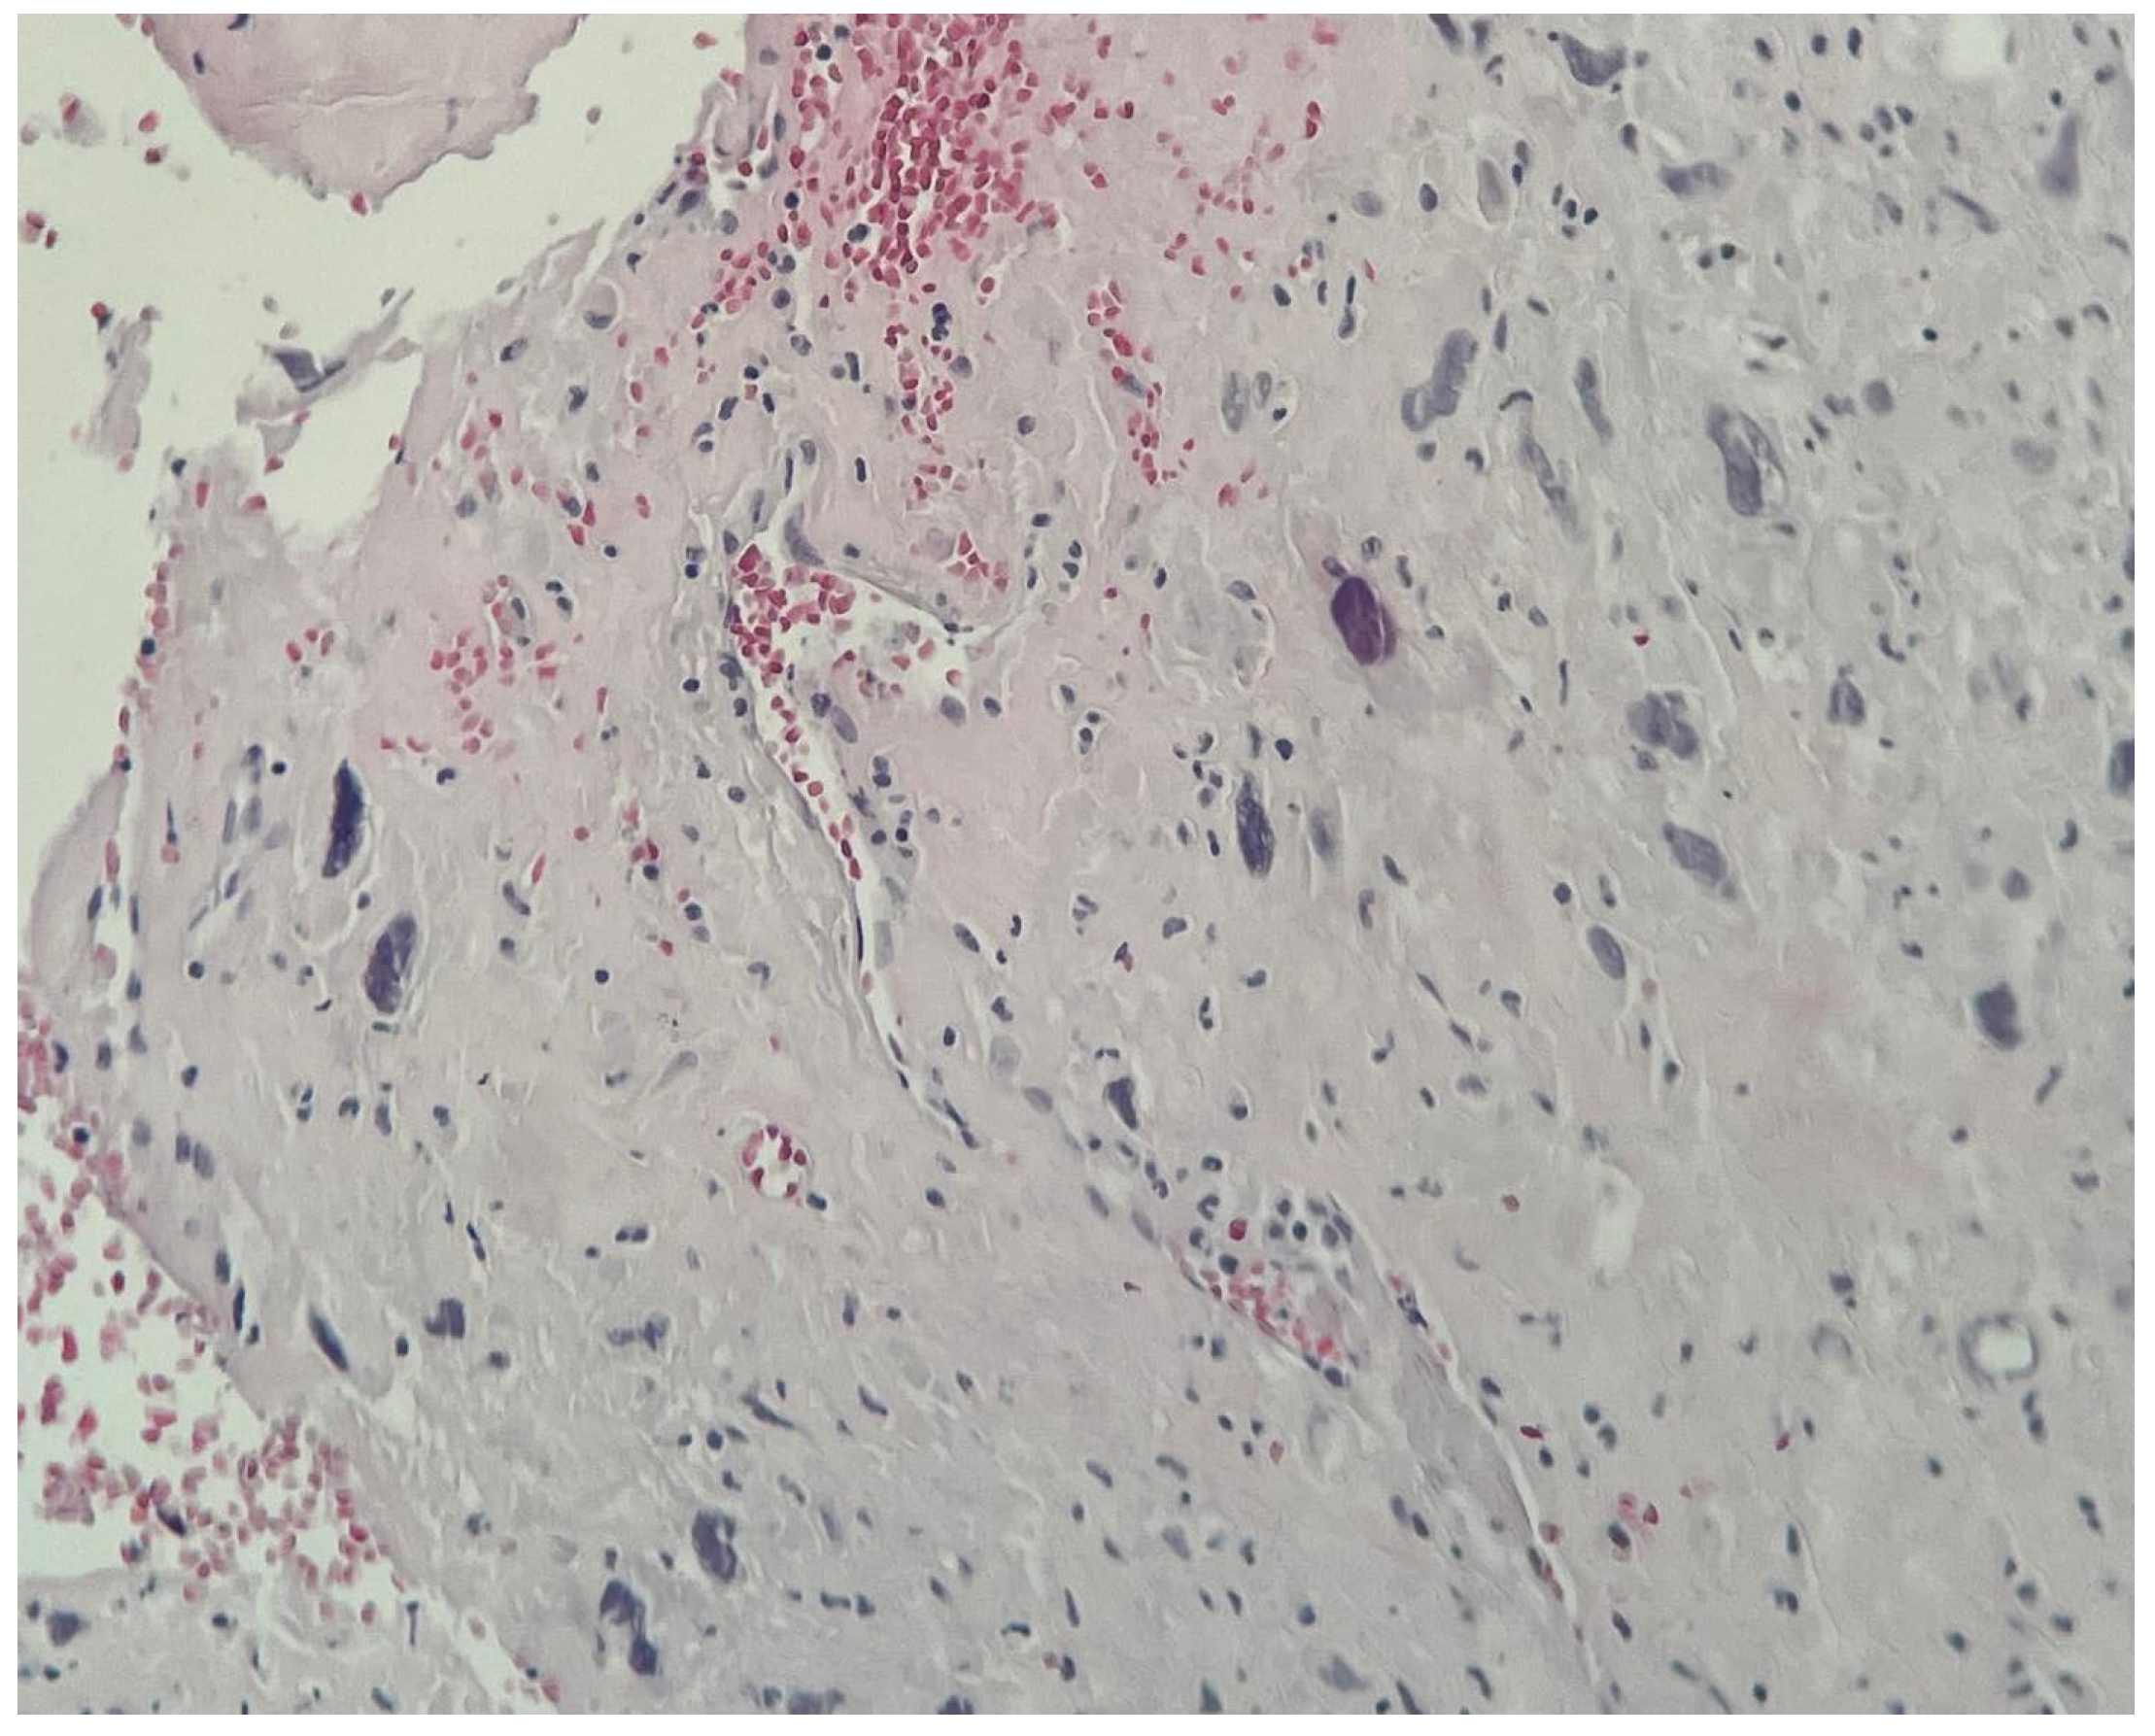

Rare Case of Grade 3 Undifferentiated Pleomorphic Sarcoma in Left Atrium, Mitral Valve, and Papillary Muscle

2. Case Report